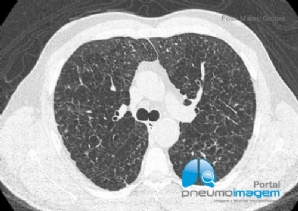

CASO CLÍNICO #58

Homem de 83 anos apresenta-se com cansaço e tosse seca persistente há 2 anos. Perdeu 5kg nos últimos 10 meses. Nega tabagismo. Qual o diagnóstico? Deixe seus comentários abaixo. *** 83-year-old man presents with tiredness and persistent dry cough for 2 y...